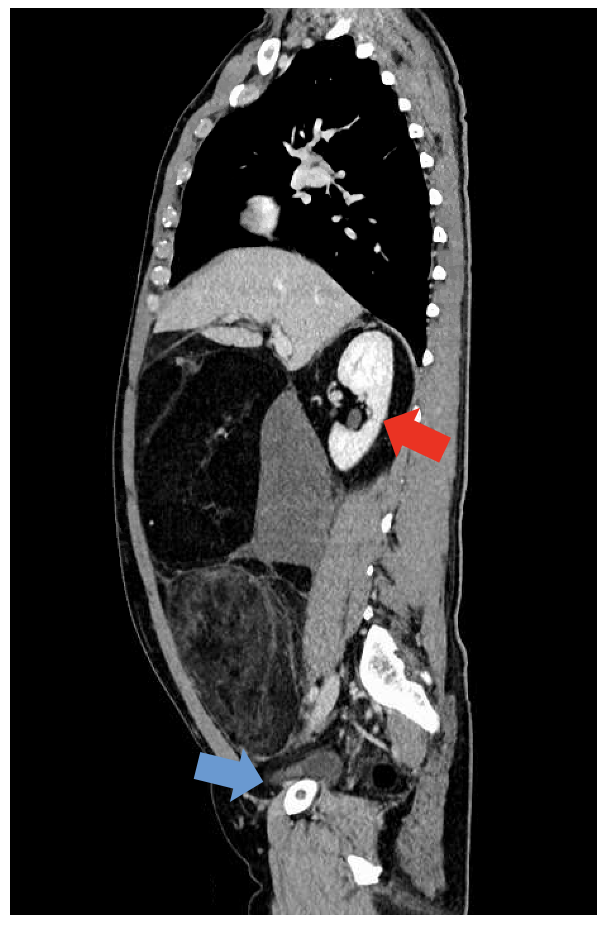

KV 127 Skelettmuskelmasse als Prädiktor für das Ansprechen auf Terlipressin bei der Behandlung des Hepatorenalen Syndroms

S. Oesinghaus1, J. Pohl1, T. Villar de Rhode1, N. Beetz2, D. Geisel2, F. Tacke1, C. Engelmann1

1Charité Campus Virchow und Campus Mitte – Universitätsmedizin Berlin, Klinik für Innere Medizin m.d.S. für Gastroenterologie und Hepatologie, Berlin, Deutschland, 2Charité – Universitätsmedizin Berlin, Klinik für Radiologie, Berlin, Deutschland

Einleitung: Das Hepatorenale Syndrom (HRS) ist eine schwere Form des akuten Nierenversagens bei Leberzirrhose und geht unbehandelt mit einer hohen Kurzzeit-Mortalität einher. Terlipressin in Kombination mit Albumin stellt die Standardtherapie dar. Die KI-gestützte CT-Body Composition Analyse (BCA) hat sich als vielversprechender Ansatz zur Risikostratifizierung bei Leberzirrhose etabliert, wodurch sie das Potenzial zur frühzeitigen Identifikation vulnerabler Patient:innengruppen bietet.

Ziele: Ziel der Studie ist es, prognostische Faktoren für das transplantationsfreie Überleben zu untersuchen und mithilfe der BCA prädiktive Marker für das Terlipressinansprechen zu identifizieren.

Methodik: Retrospektiv wurden 121 Patient:innen mit HRS eingeschlossen, die zwischen 2018 und 2022 eine Terlipressintherapie erhielten. Das Therapieansprechen wurde nach 14 Tagen anhand dreier Definitionen evaluiert: (1) Rückgang des Serumkreatinins auf ±0,3 mg/dl des Ausgangswerts, (2) Reduktion des Peak-Serumkreatinins um ≥25 %, (3) Verbesserung der Nierenfunktion um ≥1 ANV-Stadium. Anhand der BCA wurde die Muskelfläche auf L3-Höhe erhoben, indexiert [cm²/m²] und der Skelettmuskelindex (SMI) berechnet. Regressions- und Competing-Risk-Analysen identifizierten unabhängige Prädiktoren für das Terlipressinansprechen und das transplantationsfreie Überleben nach 12 Monaten.

Ergebnis: Der mittlere SMI betrug bei Männern 39,2 ± 8,7 cm²/m² und bei Frauen 35,9 ± 6,0 cm²/m². Nach 12 Monaten waren 66 der 121 Patient:innen (54,5 %) verstorben und 6 (5,0 %) lebertransplantiert. Das Terlipressinansprechen betrug 29,8 %, 45,5 % bzw. 47,1 % entspr. der Definitionen 1–3. In der Competing-Risk-Analyse war ein Therapieansprechen gem. aller drei Definitionen mit einem signifikant besseren transplantationsfreien Überleben nach 12 Monaten assoziiert. Ein Abfall des Peak-Serumkreatinins um mindestens 25% bis Tag 14 erwies sich hierbei als stärkster Prädiktor (HR 0,25; KI-95% 0,14-0,42; p < 0,0001). In den multivariaten COX-Modellen war ein niedriger SMI ein robuster unabhängiger Prädiktor für ein fehlendes Terlipressinansprechen gem. Definition (2) (HR 1,95; KI-95% 1,24-3,07; p < 0,01).

Schlussfolgerung: Die Muskelmasse, gemessen am SMI, ist ein unabhängiger Prädiktor für das Ansprechen auf Terlipressin bei der Behandlung des HRS. Größere multizentrische Studien sind jedoch notwendig, um Patient:innen mit unzureichendem Therapieansprechen anhand dessen zu identifizieren.

09:18 – 09:24